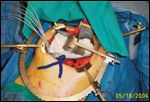

FIGURE 2

Intraoperative Radiation TherapyFIGURE 3

HAM Applicator

Intraoperative radiotherapy (IORT) is a technique that delivers single high-dose irradiation to a tumor at surgery. Because the tumor and surrounding normal tissues are directly visualized, nontarget tissues can be shielded or excluded from the IORT field. Low-energy photons (eg, Ir-192) or electrons are typically used for IORT, allowing rapid dose falloff with distance, resulting in minimal dose to the surrounding normal critical structures. Small bowel, stomach, duodenum, liver, and other normal structures can be directly shielded or displaced during the procedure, thus sparing these tissues. Additionally, tumor or tumor-bearing tissues outside the biliary system can be treated. IORT doses range from 10 to 20 Gy in a single fraction. This is usually combined with a course of EBRT dose of 45 to 50.4 Gy over 25 to 28 fractions. Figures 2 and 3 demonstrate the use of IORT with an Ir-192 source via a Harrison-Anderson-Mick (HAM) applicator.